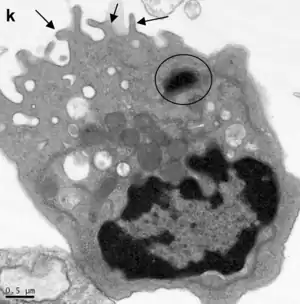

Ultraestructura

Con microscopía electrónica se destaca un extremo apical con microvellosidades cortas y escasas en la luz del bronquiolo.

El retículo endoplasmático es abundante, el aparato de Golgi y los gránulos densos apicales presentan todas las características de una célula de producción y secreción proteica.

El retículo endoplasmático liso genera numerosas vesículas supranucleares.[1]

Las mitocondrias son cortas y numerosas ubicadas en el compartimiento supranuclear.